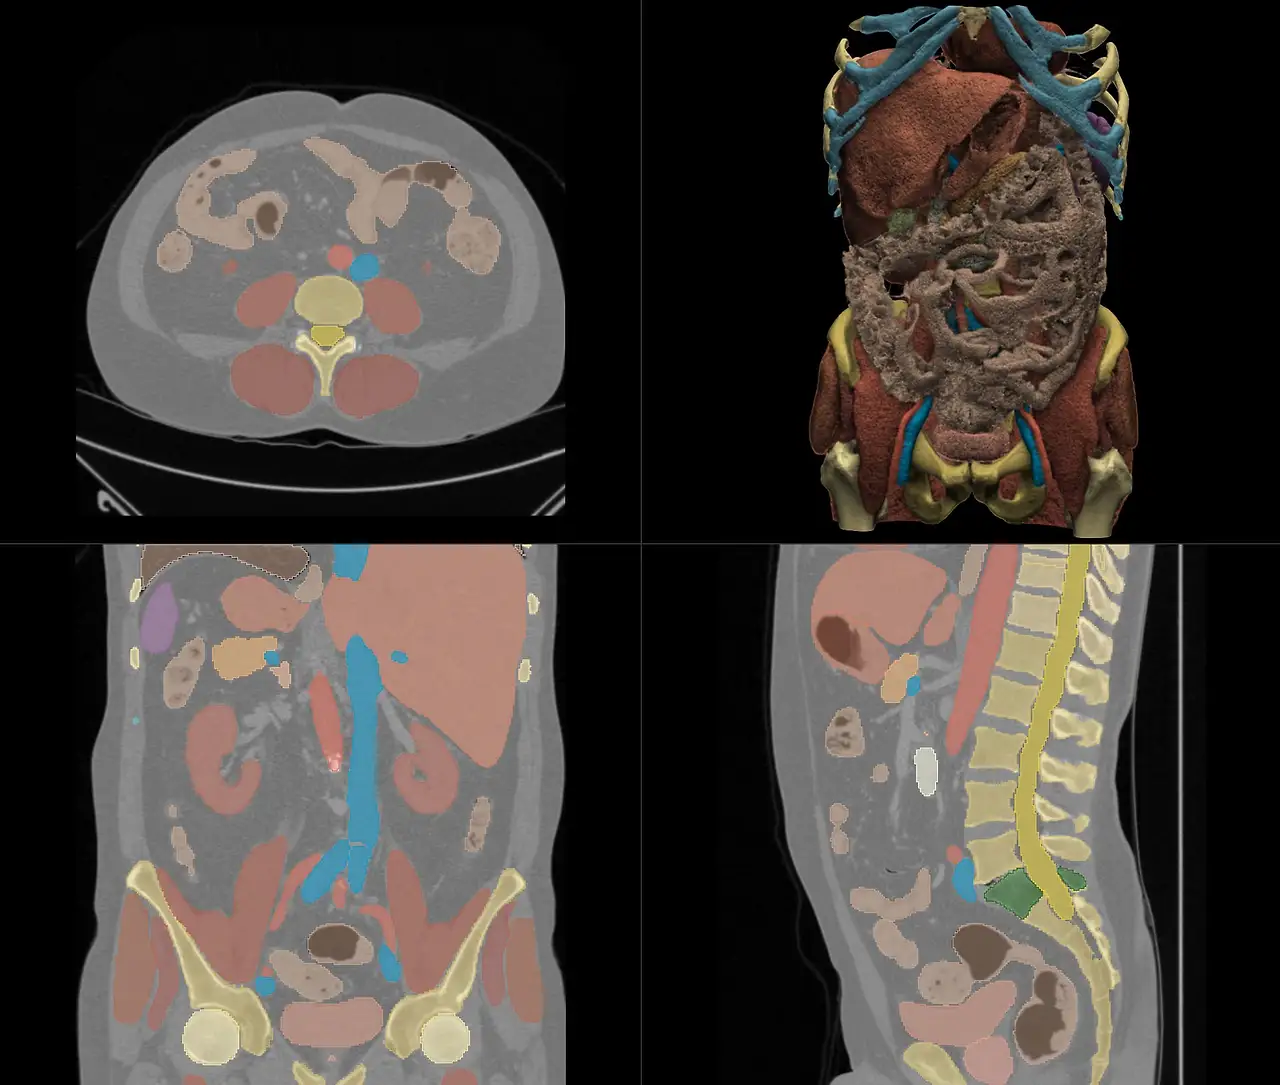

이런 걸 직접 뽑아내 보는 중이다. 간단히 말해, 신체 분리쇼를 코드로 간단하게 실행하도록 설계하는 거다, Wow! TotalSegmentator라는 오픈소스 프로그램을 통해(사실 CLI 기반이라고 했을 때부터 설마 내가 직접 코딩해야 하는 건가... 라는 쎄함을 느꼈지만) 딥러닝 정보와 같이 저런 식으로 장기들을 분해해주는 매우 고마운 코드이다. 이게... 중요한 점은 무료라는 것, 그리고 은근 기능도 많고 정확도도 꽤나 높다는 점.

우리 연구실은 이것에 집중해보는 편이라고 보면 되겠다. 다만, 이것만 하는 게 아니라 더 나아가 '암 예측 프로토콜'과 같은 예측 연구를 진행하기에, 어쩌면 이것도 매우 매우 매우 작은 연구의 일환이 아닐까. 난 이런 연구를 하고 있다... 정도를 뽐내고 싶었던 나의 잡글. 사실, 오늘은 이 Contouring을 fine tuning하는 작업을 했는데 왜 이리 마우스는 뻑뻑하고 손은 내 말을 안 따르고, Slice 수는 뭐 이리 많은지... 선임 누나도 한 시간에 한 케이스를 할 정도라고 하니 익숙하지 않은 나는 얼마나 또 갈려야 할까...